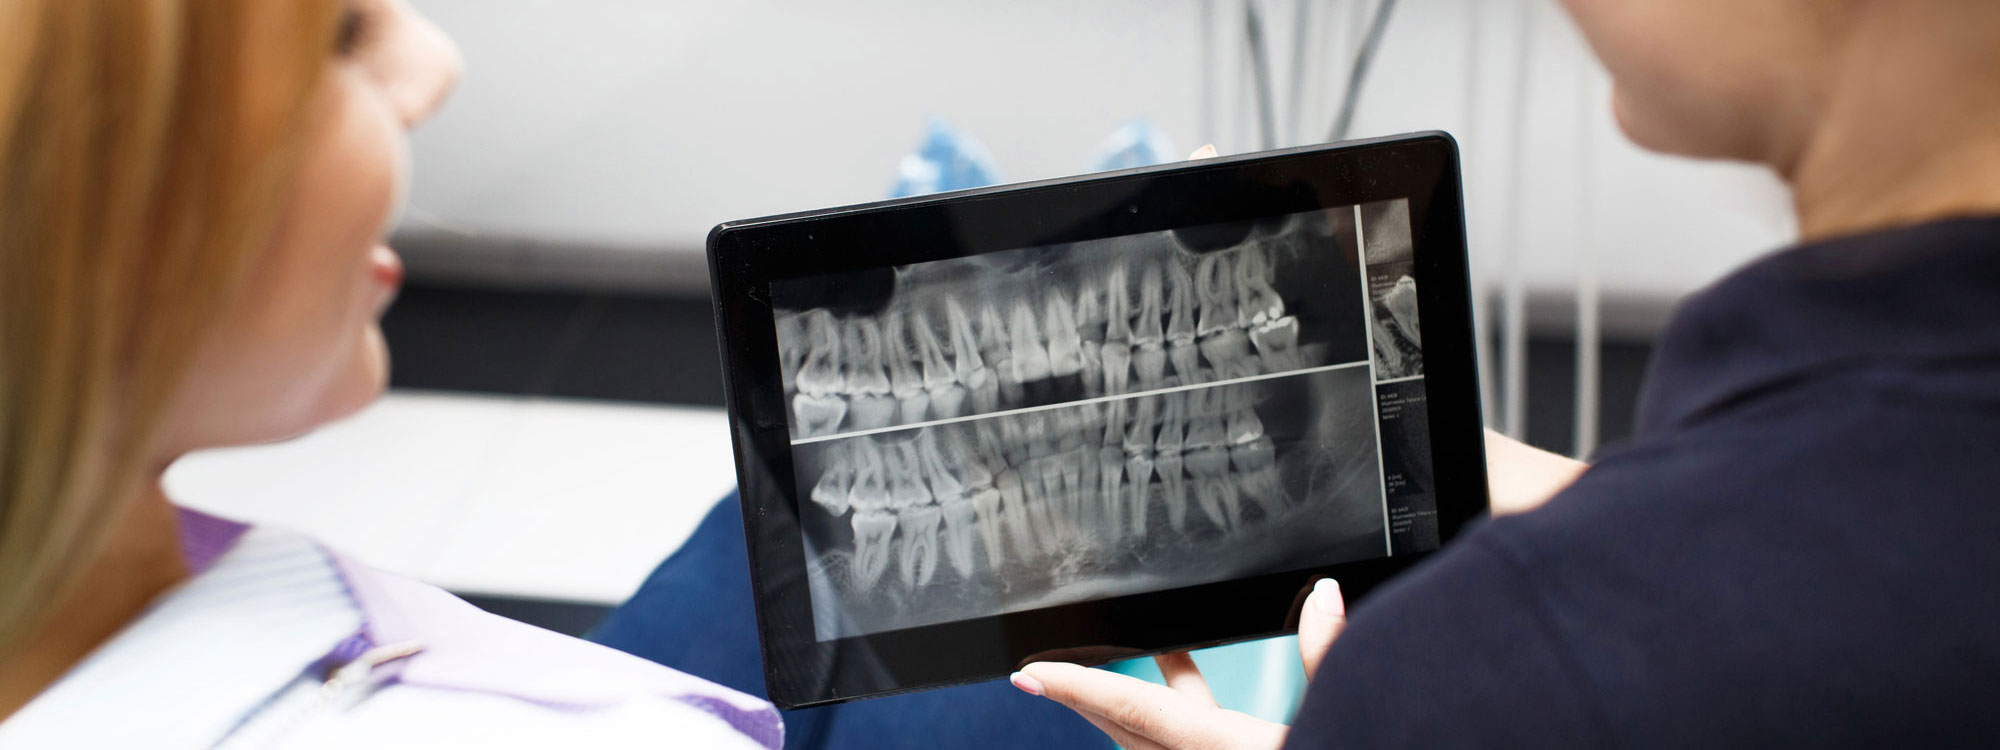

За точна дијагноза и третман насочен кон целта, потребно е да се погледне во внатрешноста на забот. За таа цел нудиме широк спектар на опции за оваа намена.

Преку нашите истражувачки активности, нашиот тим е запознаен со најновите научни наоди и може да ги исполни највисоките технолошки и професионални очекувања. За прегледи и проценки, имаме широк спектар на опции. Користиме различни методи за сликање, како што се проекциона радиографија, томографија и компјутерска томографија.

Kористиме најнова технологија за да овозможиме прецизен третман за нашите пациенти преку методи на снимање.